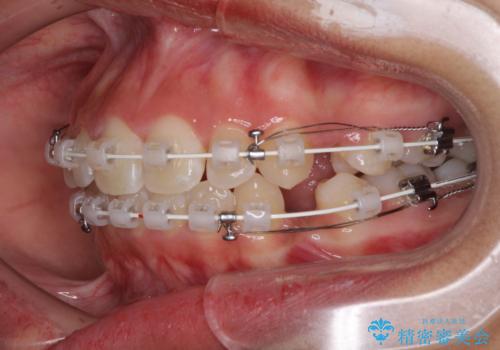

- 審美装置

- 1年7ヶ月

- 10-30回

前歯部の突出と開咬は、舌突出癖によるものでしたので、舌のトレーニングをしっかりと行っていただき、1年半程度と短期間で治療を終えることができました。